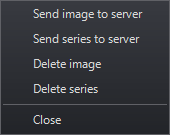

Users with Edit or Report permissions can upload exported MPR images and series to the server so other users can use them.

Once an exported image is saved to the server, you can attach it to a report as a key image.